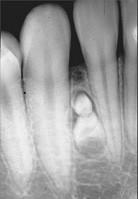

问题 组图为牙瘤的外观及X 线表现,有关此病的描述错误的是 ( )

选项 A.绝大多数为恶性 B.生长缓慢,早期无自觉症状 C.由牙胚组织异常发育增生而形成 D.X 线可见类似发育不全牙的影像 E.多见青年人

答案 A